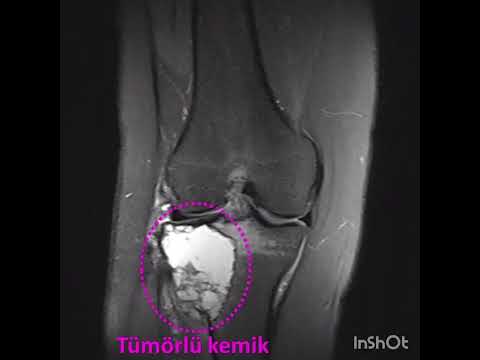

Kemik tümörlerinin tanısında basit röntgenler çok önem taşır ve doğru şekilde değerlendirildiğinde yeterli olabilir. Ancak kötü huylu olabileceği düşünülen ya da yumuşak doku tümörlerinde mutlaka MR çekilmelidir. MR kontrastlı olmalı ve yeterli kalitede olacak şekilde çekilmelidir. Aksi halde hasta tekrar MR çektirmek zorundadır. Kemik tümörlerinde zaman zaman bilgisayarlı tomografiden de yararlanılır. Ayrıca kemik taraması isteniyorsa, ya da tümörün diğer kemiklere yayılıp yayılmadığının anlaşılabilmesi için kemik sintigrafisi de önem taşır. PET ise son derece özel bir görüntüleme yöntemi olup henüz tanı almamış hastalar için yeri yoktur.